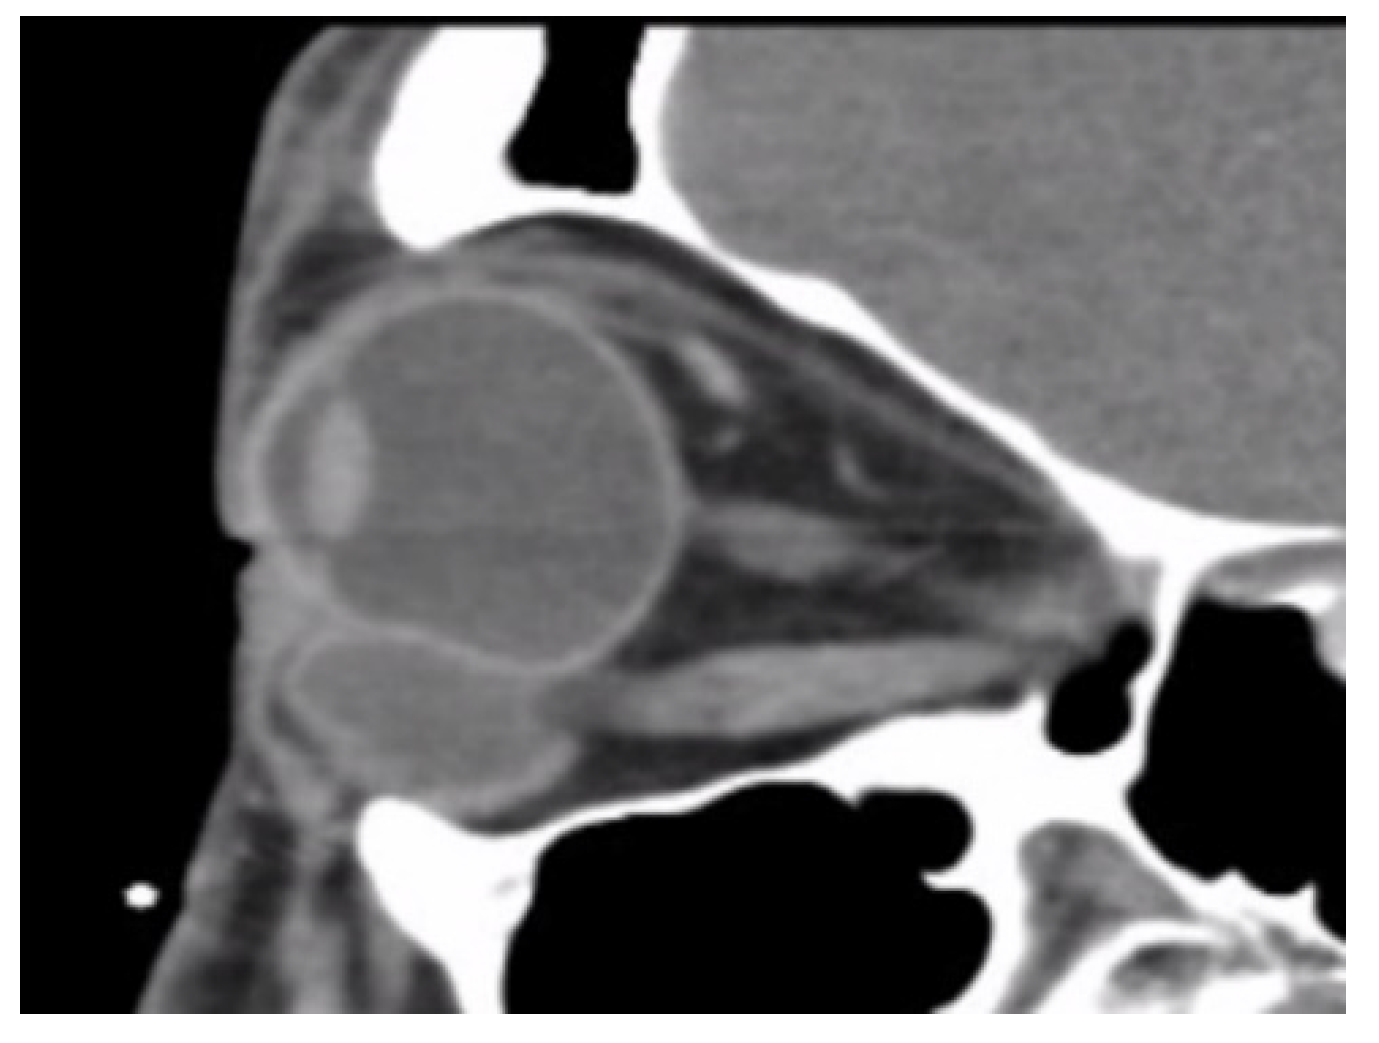

Location of HSB was categorized into groups according to the relative location to the globe equator in orbit-computed tomography (CT): anterior-located and posterior-located HSB. Anterior-located HSB were defined as more than 50% of HSB coverage anterior to the globe equator in sagittal cut, while the others were defined as posterior-located HSB.

In total, we collected eleven cases; Table 1 summarizes the clinical data. One patient had bulbar atrophy before the diagnosis of swollen HSB (Figure 1). Table 2 shows the presenting symptoms of the patients. The symptoms included limitation of extraocular movement (ten eyes, 90.9%), ocular redness (eight eyes, 72.7%), ocular fullness (eight eyes, 72.7%), pain (six eyes, 54.5%), and exposed ocular foreign body (five eyes, 45.5%). Six patients (54.5%) received a correct diagnosis when referred to the medical center. Initial diagnoses other than swollen HSB included eyeball rupture (one eye, 9.1%), and orbital tumor (four eyes, 36.4%). Six patients (54.5%) had glaucoma in the diseased eyes and were treated with at least one combined form or two antiglaucoma medications before orbital HSB swelling was found. Four patients (66.7%) were male, but there was no significance of sex and glaucoma correlation according to Chi-Square analysis (p = 0.652). In the six patients with glaucoma, four cases had inadequate IOP control and one case received minimally invasive glaucoma surgery due to uncontrolled IOP one year before HSB removal. New onset of limitations of extraocular movement prompted the doctors to survey for orbital lesions. The typical CT image finding of HSB is a circumferential and homogenous mass around the globe. As this material usually swells when it absorbs water and forms a pseudocapsule around itself, CT images show an isointense signal with a vitreous and non-infiltrative lesion that deforms the eyeball. A scattered, and hyperintense signal, which corresponds to calcific change, can also be found around the swollen HSB (Figure 2). In MRI study, the HSB usually show hypointensity in T1-weighted images and hyperintensity in T2-weighted images, as these materials absorb water (Figure 3). According to the location of HSB in orbital CT, we categorized the HSB coverage into two groups: anterior-located (Figure 4) and posterior-located HSB (Figure 5). In the six patients with glaucoma, four (66.7%) showed posterior-located HSB. However, Fisher’s exact test of the relationship between the posterior-located HSB and glaucoma diagnosis did not reach clinical significance (p = 0.061).

Figure 5. Orbital CT at sagittal view revealed posteriorly located hydrogel scleral buckles.

It is worth mentioning that none of the previous studies mentioned glaucoma status or refractory IOP before removal of the implant. In our study, six patients had glaucoma, and four of them had inadequate IOP control. There are two possible explanations for this. First, these patients had a longer interval between HSB implantation surgery and removal, ranging from 26 to 30 years. Previous large-population studies documented the interval between implantation and removal from 8 to 23 years [3,6,17]. With an extended period in our study, pathological changes in periorbital tissue such as fibrotic change, impaired ocular circulation and ocular compression, can play a role in glaucomatous development. Another explanation is that the relative location and degrees of HSB coverage may influence the development of glaucoma. Four out of the six cases with glaucoma in our study showed HSB coverage posterior to the equator. Compared to the anterior location, posteriorly located HSB cannot release the swelling pressure through protrusion of the orbital exit. Previous studies documented the degrees of HSB coverage but not the relative location to the equator. Roldán-Pallarés et al. followed up 415 cases with hydrogel implantation for up to seven years [17]. More than half of the patients received HSB coverage over 180 degrees, and 45% of the patients had 360-degree encircling HSB coverage. None of these patients reported elevated IOP or glaucoma status, but unspecified orbital fullness was noted in only six cases. These may imply that the relative location compared to the globe equator, not the range of HSB coverage, may be the key factor that influences IOP. The relationship between IOP elevation and the location of swelling HSB must be proven through further studies.